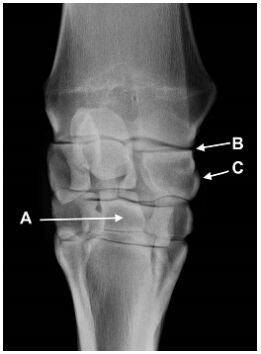

3.下圖為馬前肢放射線影像圖,下列敘述何者正確? (A)圖之右側為外側 (B)A 為 3rd metacarpal bone (C)B 為 carpometacarpal joint (D)C 為 radial carpal bone